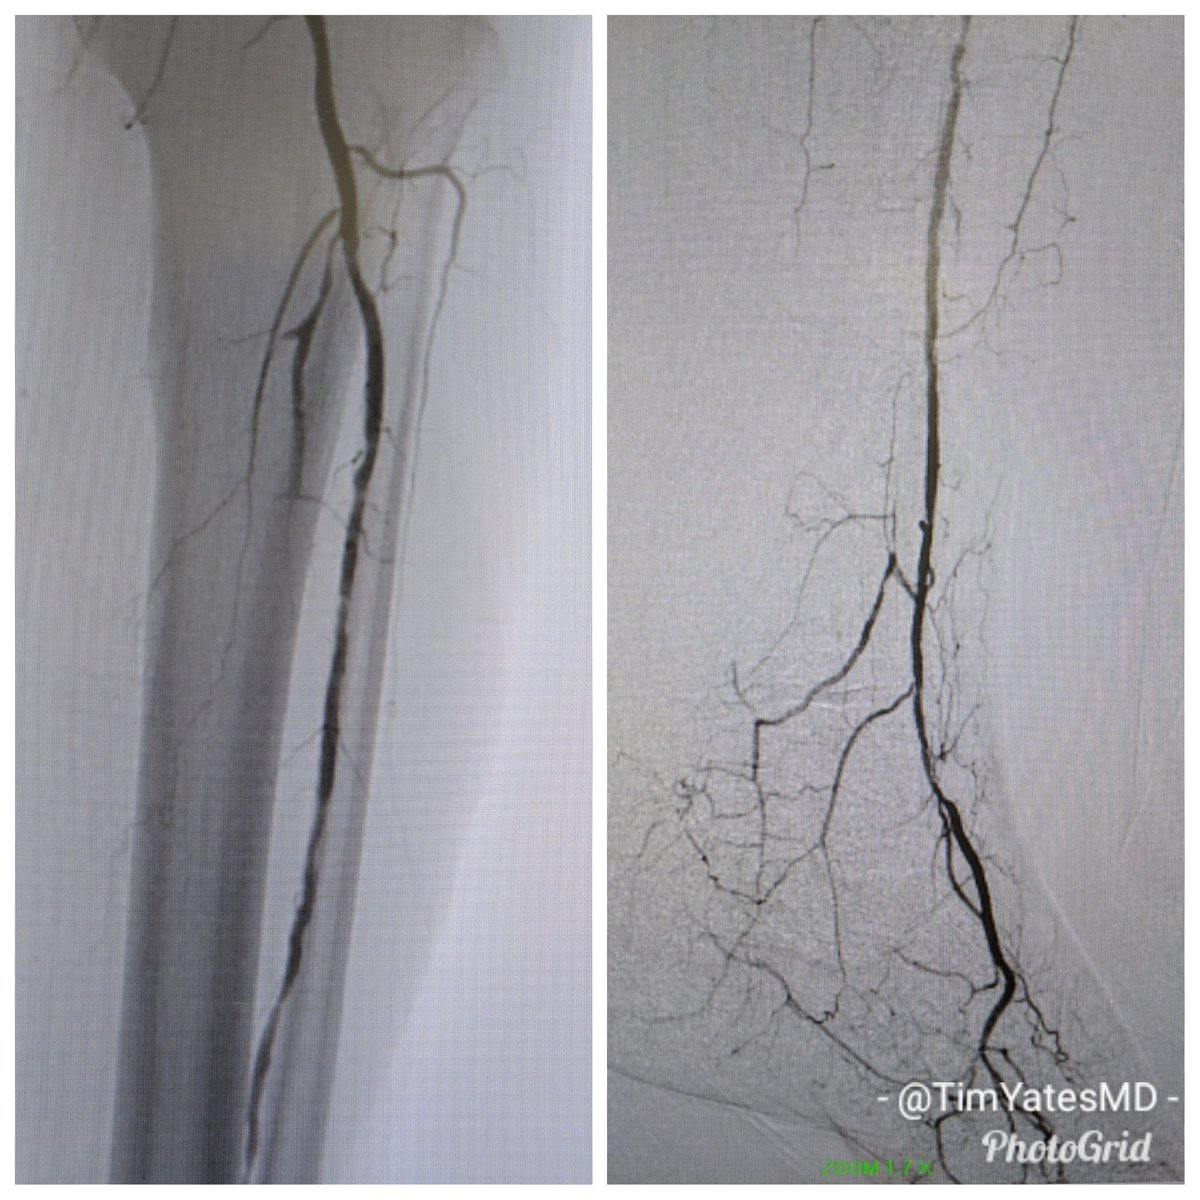

Great day for 3 vessel runoff and a complete pedal plantar loop. RC5 L 2-4 toe #CLI after degloving injury. #CSI @belzerj @AbbottGlobal #commandwire @CLI_Global @CLIfighters #CLIfighters @FadiSaab17 @Mustapja @SIRspecialists @SIRRFS @SIR_ECS @SriniTummala @kmadass @BOlivieriMD